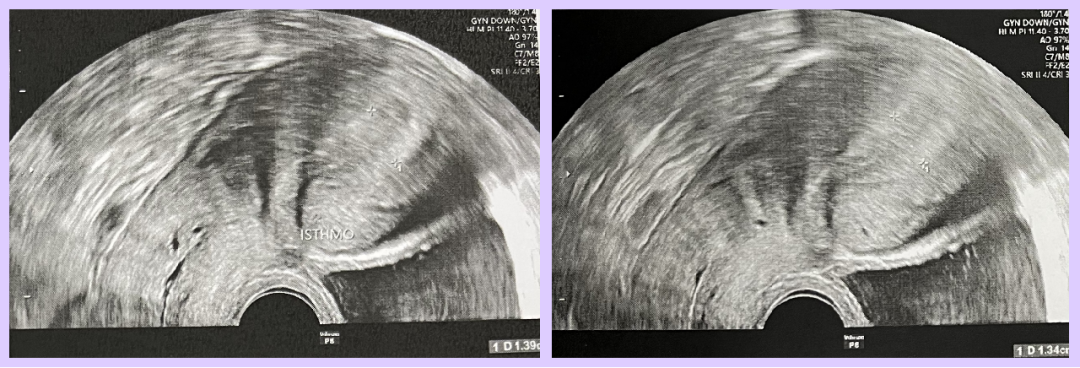

▲ Ms. L’s blastocyst culture report

Embryo Development Results

- Oocytes Retrieved: 16

- Mature Eggs: 14

- Normally Fertilized: 13

- Day 3: 9 embryos with 8 cells, 2 with 6 cells, 2 with 4 cells

- Day 5: 10 blastocysts formed and biopsied

- Chromosomal Screening: 2 normal embryos